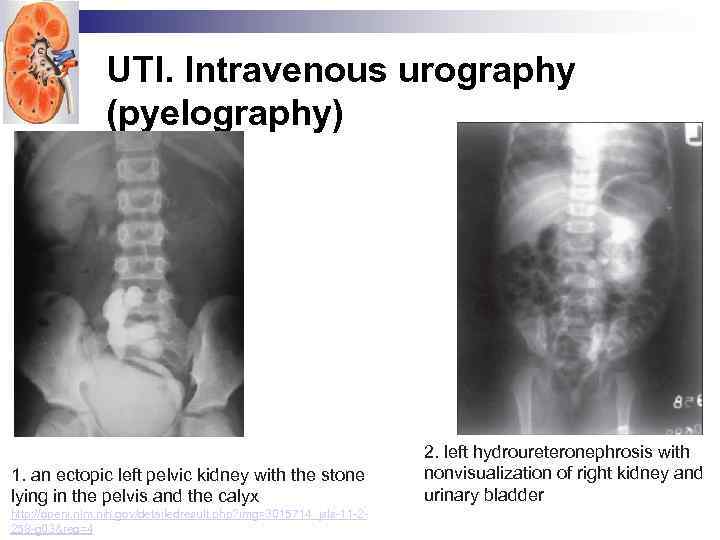

UTI. Intravenous urography (pyelography) 1. an ectopic left pelvic kidney with the stone lying in the pelvis and the calyx http: //openi. nlm. nih. gov/detailedresult. php? img=3015714_jsls-11 -2258 -g 03&req=4 2. left hydroureteronephrosis with nonvisualization of right kidney and urinary bladder

UTI. Intravenous urography (pyelography) 1. an ectopic left pelvic kidney with the stone lying in the pelvis and the calyx http: //openi. nlm. nih. gov/detailedresult. php? img=3015714_jsls-11 -2258 -g 03&req=4 2. left hydroureteronephrosis with nonvisualization of right kidney and urinary bladder